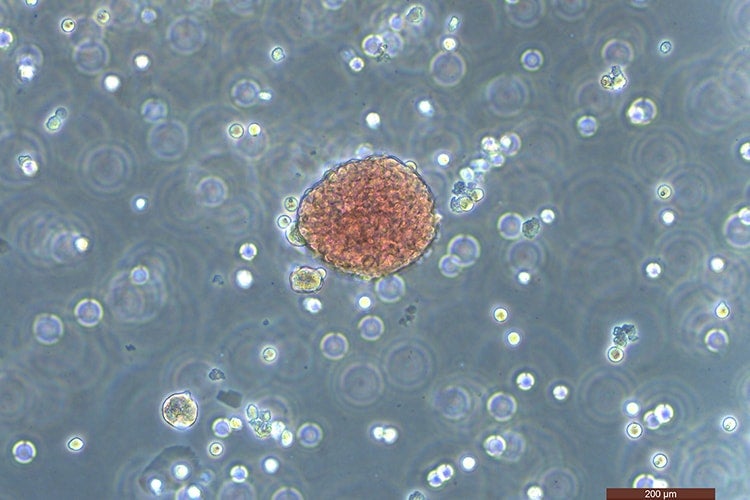

Researchers derived this colony of red blood cells from pluripotent stem cells (photo by Jelena Tomic)

At best, one cell in a hundred becomes the desired blood-forming cell, with the other 99 turning into something else. “It’s really tricky growing these cells because they take on other identities and change on you at any given time,” says Jelena Tomic, a scientific associate who is splitting time between Moffat’s and Keller’s labs.